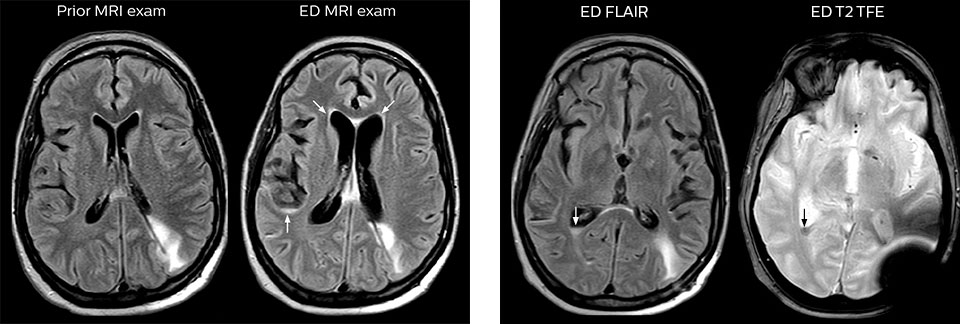

When neurological emergencies require diagnostic imaging, common practice in the ED has been to perform CT rather than MRI, even when MRI could potentially produce more informative diagnostic images of spinal cord damage, disc protrusions, soft tissue injuries, and stroke pre-cursors. [1,2] The main reason is that timing is essential in emergency cases, and CT is generally faster than MRI. The St. Joseph’s Hospital and Medical Center is now challenging this paradigm by offering rapid MRI scans within its Neurologic ED and seeing that it helps them make a richer diagnosis.

efficient as CT for referring physicians, then physicians would probably prefer MRI over CT in part of the cases. Reducing the number of CT scans for patients less than 40 years of age without significant acute findings, such as acute stroke, was also a main reason for introducing MRI into the ED. “MRI is a better test for identifying soft tissue abnormalities in the brain. What really influenced the decision on the administrative side, was the total radiation dose received by ED patients, and how this could be reduced by introducing MRI in the ED”.

“In the past, CT scans were performed because of their availability and rapid turnaround time” Dr. Karis argues, “but if an MRI could be as efficient as CT for referring physicians, then physicians would probably prefer MRI over CT in part of the cases. Reducing the number of CT scans for patients less than 40 years of age without significant acute findings, such as acute stroke, was also a main reason for introducing MRI into the ED. “MRI is a better test for identifying soft tissue abnormalities in the brain. What really influenced the decision on the administrative side, was the total radiation dose received by ED patients, and how this could be reduced by introducing MRI in the ED”.

“One of the most important decisions an ED physician has to make is to admit or discharge their patient. So a physician who is better informed by an MRI exam can make this decision with more confidence. By converting to a test that has a far better potential to identify issues, physicians get a better and more certain diagnosis."

"In my experience a negative MRI, because it is so sensitive to abnormality, far exceeds the value of a negative CT. A negative MRI can allow physicians to be more confident about making discharge decisions, potentially reducing the number of admissions in cases of doubt, and offering cost savings for the institute."